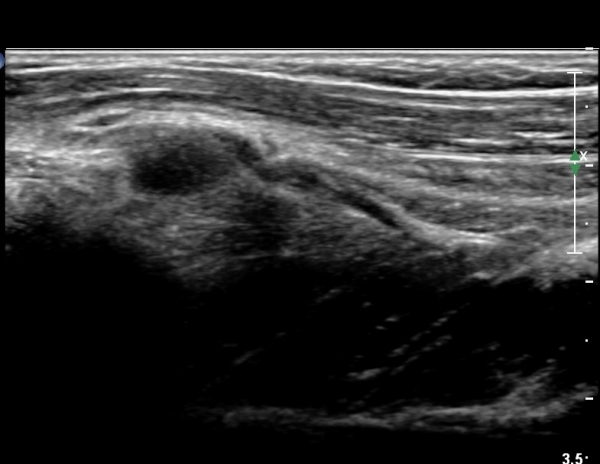

¿Ü»ó°ú¿¡¼­ ¼Õ¸ñ ½ÅÀü°Ç ´ÜµÎ Á¾´Ü¸é°Ë»ç¿¡¼­ ƯÀÌ ¼Ò°ßÀ» º¸ÀÌÁö ¾Ê´Â´Ù(»çÁø 1, 2)

¿ä°ñµÎ ºÎÀ§ ÆÈ²ÞÄ¡ ¾Õ, ¿ÜÃø Ⱦ´Ü¸é°Ë»ç¿¡¼­ Èİñ°£ ½Å°æ ³»Ãø, ¿ä°ñµÎ Ç¥Ãþ¿¡¼­

ÀÛÀº ³¶Á¾ÀÌ °üÂûµÈ´Ù(»çÁø 3)